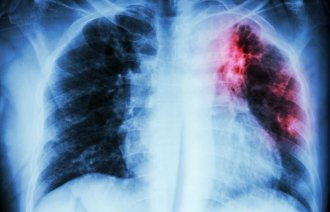

Tuberkulose: Den grå «massemorderen» herjer verden

Multiresistent tuberkulose er nå den viktigste årsaken til dødsfall globalt på grunn av antibiotikaresistens.

Tuberkulose med bakterier som er blitt motstandsdyktige mot antibiotika, er blitt et alvorlig og økende problem globalt.

– På verdensbasis utgjør multiresistent tuberkulose nå den viktigste årsaken til dødsfall som følge av antibiotikaresistens, skriver Folkehelseinstituttet i en pressemelding.